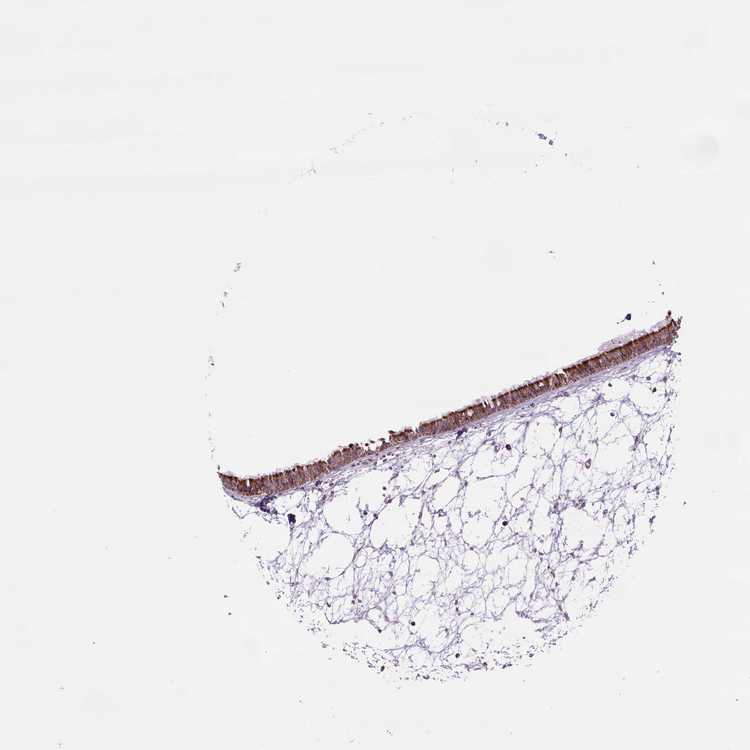

TISSUE PRIMARY DATA NASOPHARYNX Show tissue menu

NASOPHARYNX - Antibody stainingi

Antibody staining in the annotated cell types in the current human tissue is reported as not detected, low, medium, or high, based on conventional immunohistochemistry profiling in selected tissues. This score is based on the combination of the staining intensity and fraction of stained cells.

Each image is clickable and will lead to virtual microscopy that enables deeper exploration of all samples and also displays staining intensity scores, fraction scores and subcellular localization as well as patient and tissue information for each sample.

Antibody HPA069328Antibody CAB016241

Respiratory epithelial cells MediumHigh